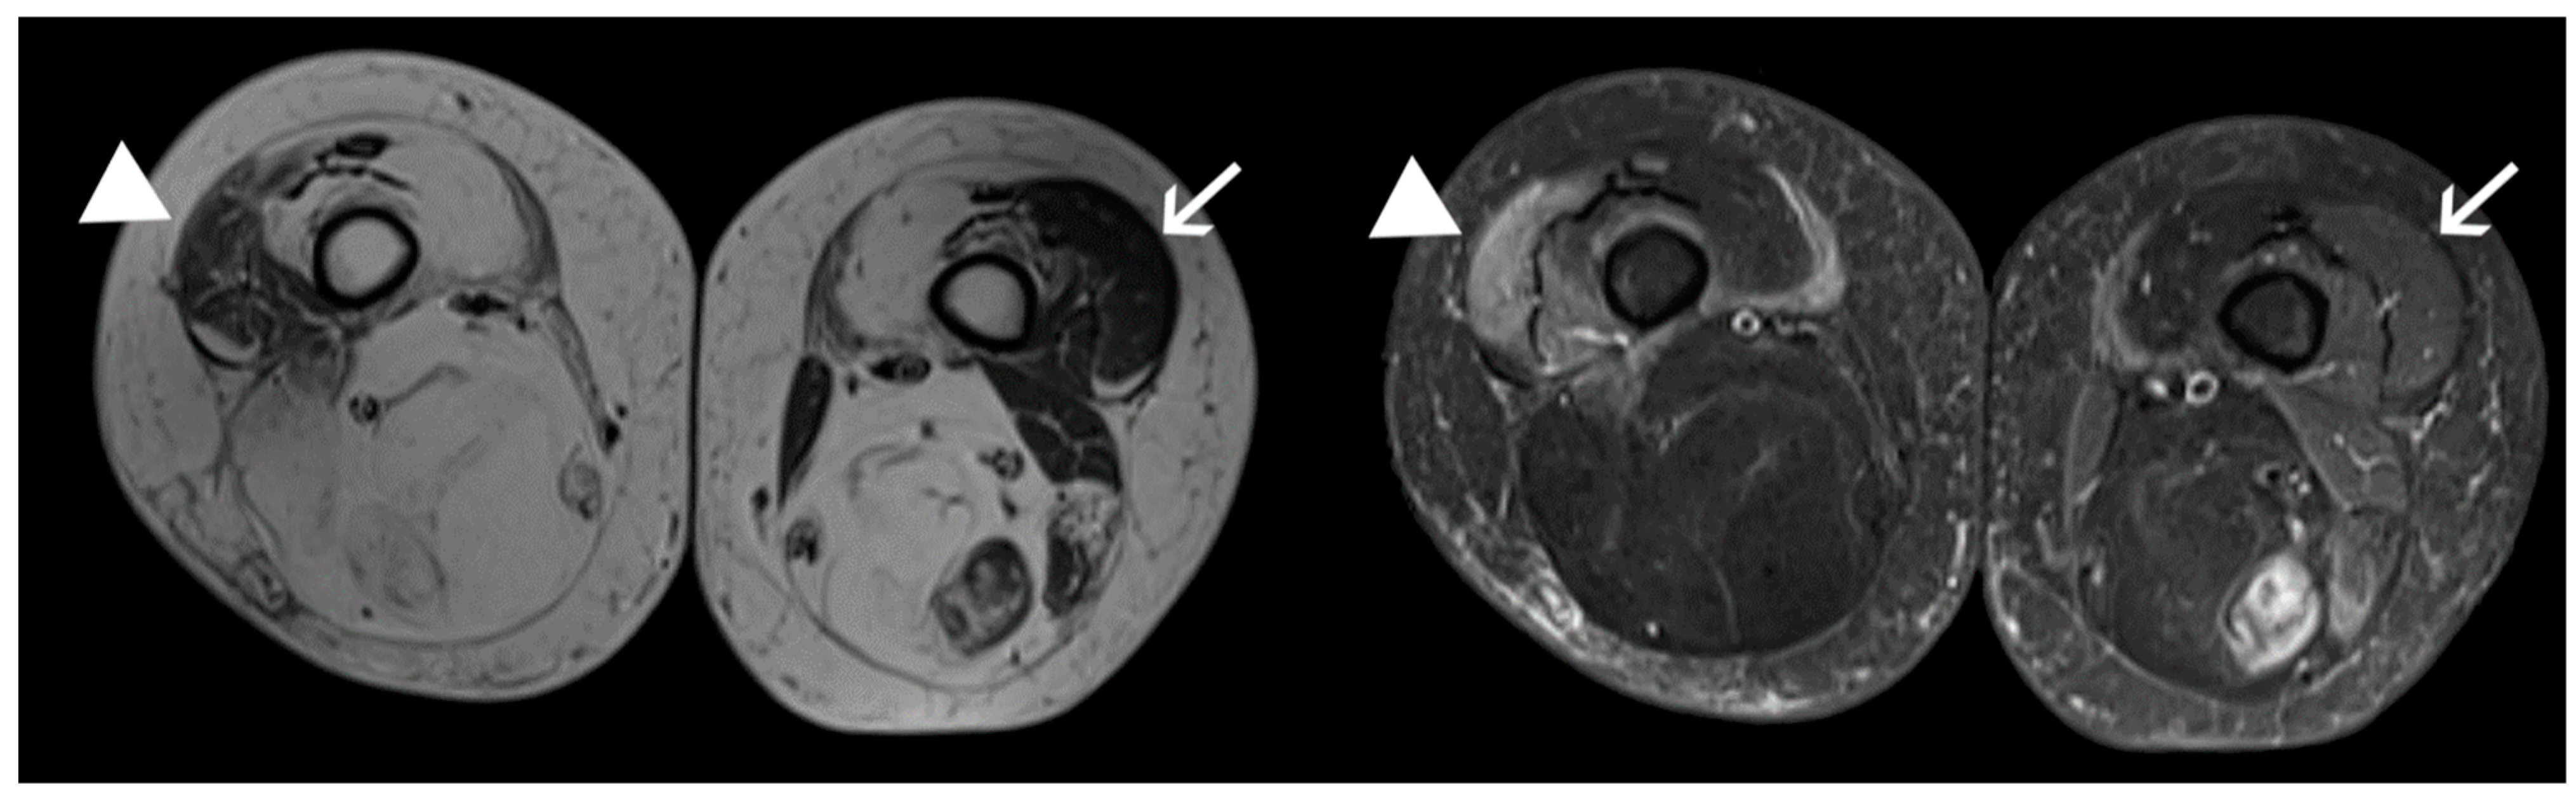

4.1. Patients and Samples